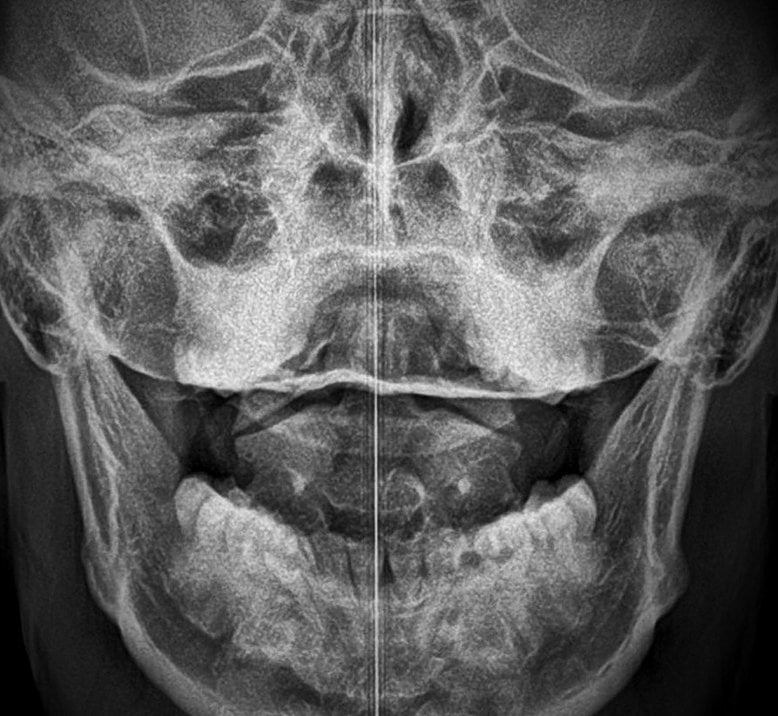

Are X-Rays necessary?

Yes. It is important that certain X-rays be made. To see is to know, to not see is to guess. An Atlas Orthogonist will never guess about your health. Our chiropractors had extensive X-ray training and will never require X-ray studies which are not vital to the diagnosis and treatment of your condition.

Are x-rays safe?

In general, cervical spine X-rays are very safe. Although any exposure to radiation poses some risk to the body, the amount used in a cervical spine X-ray is small and not considered dangerous.

Here is a comparison of the radiation dosages you would experience with our x-rays versus radiaiton you are exposed to in the environment:

The radiation exposure is extremely low with the upper cervical x-ray series, due to special lead filters that block out a majority of the radiation. The NAS (National Academy of Sciences) considers a single exposure of the whole body of 50,000 mrems (50 rems) to be a high level dose.